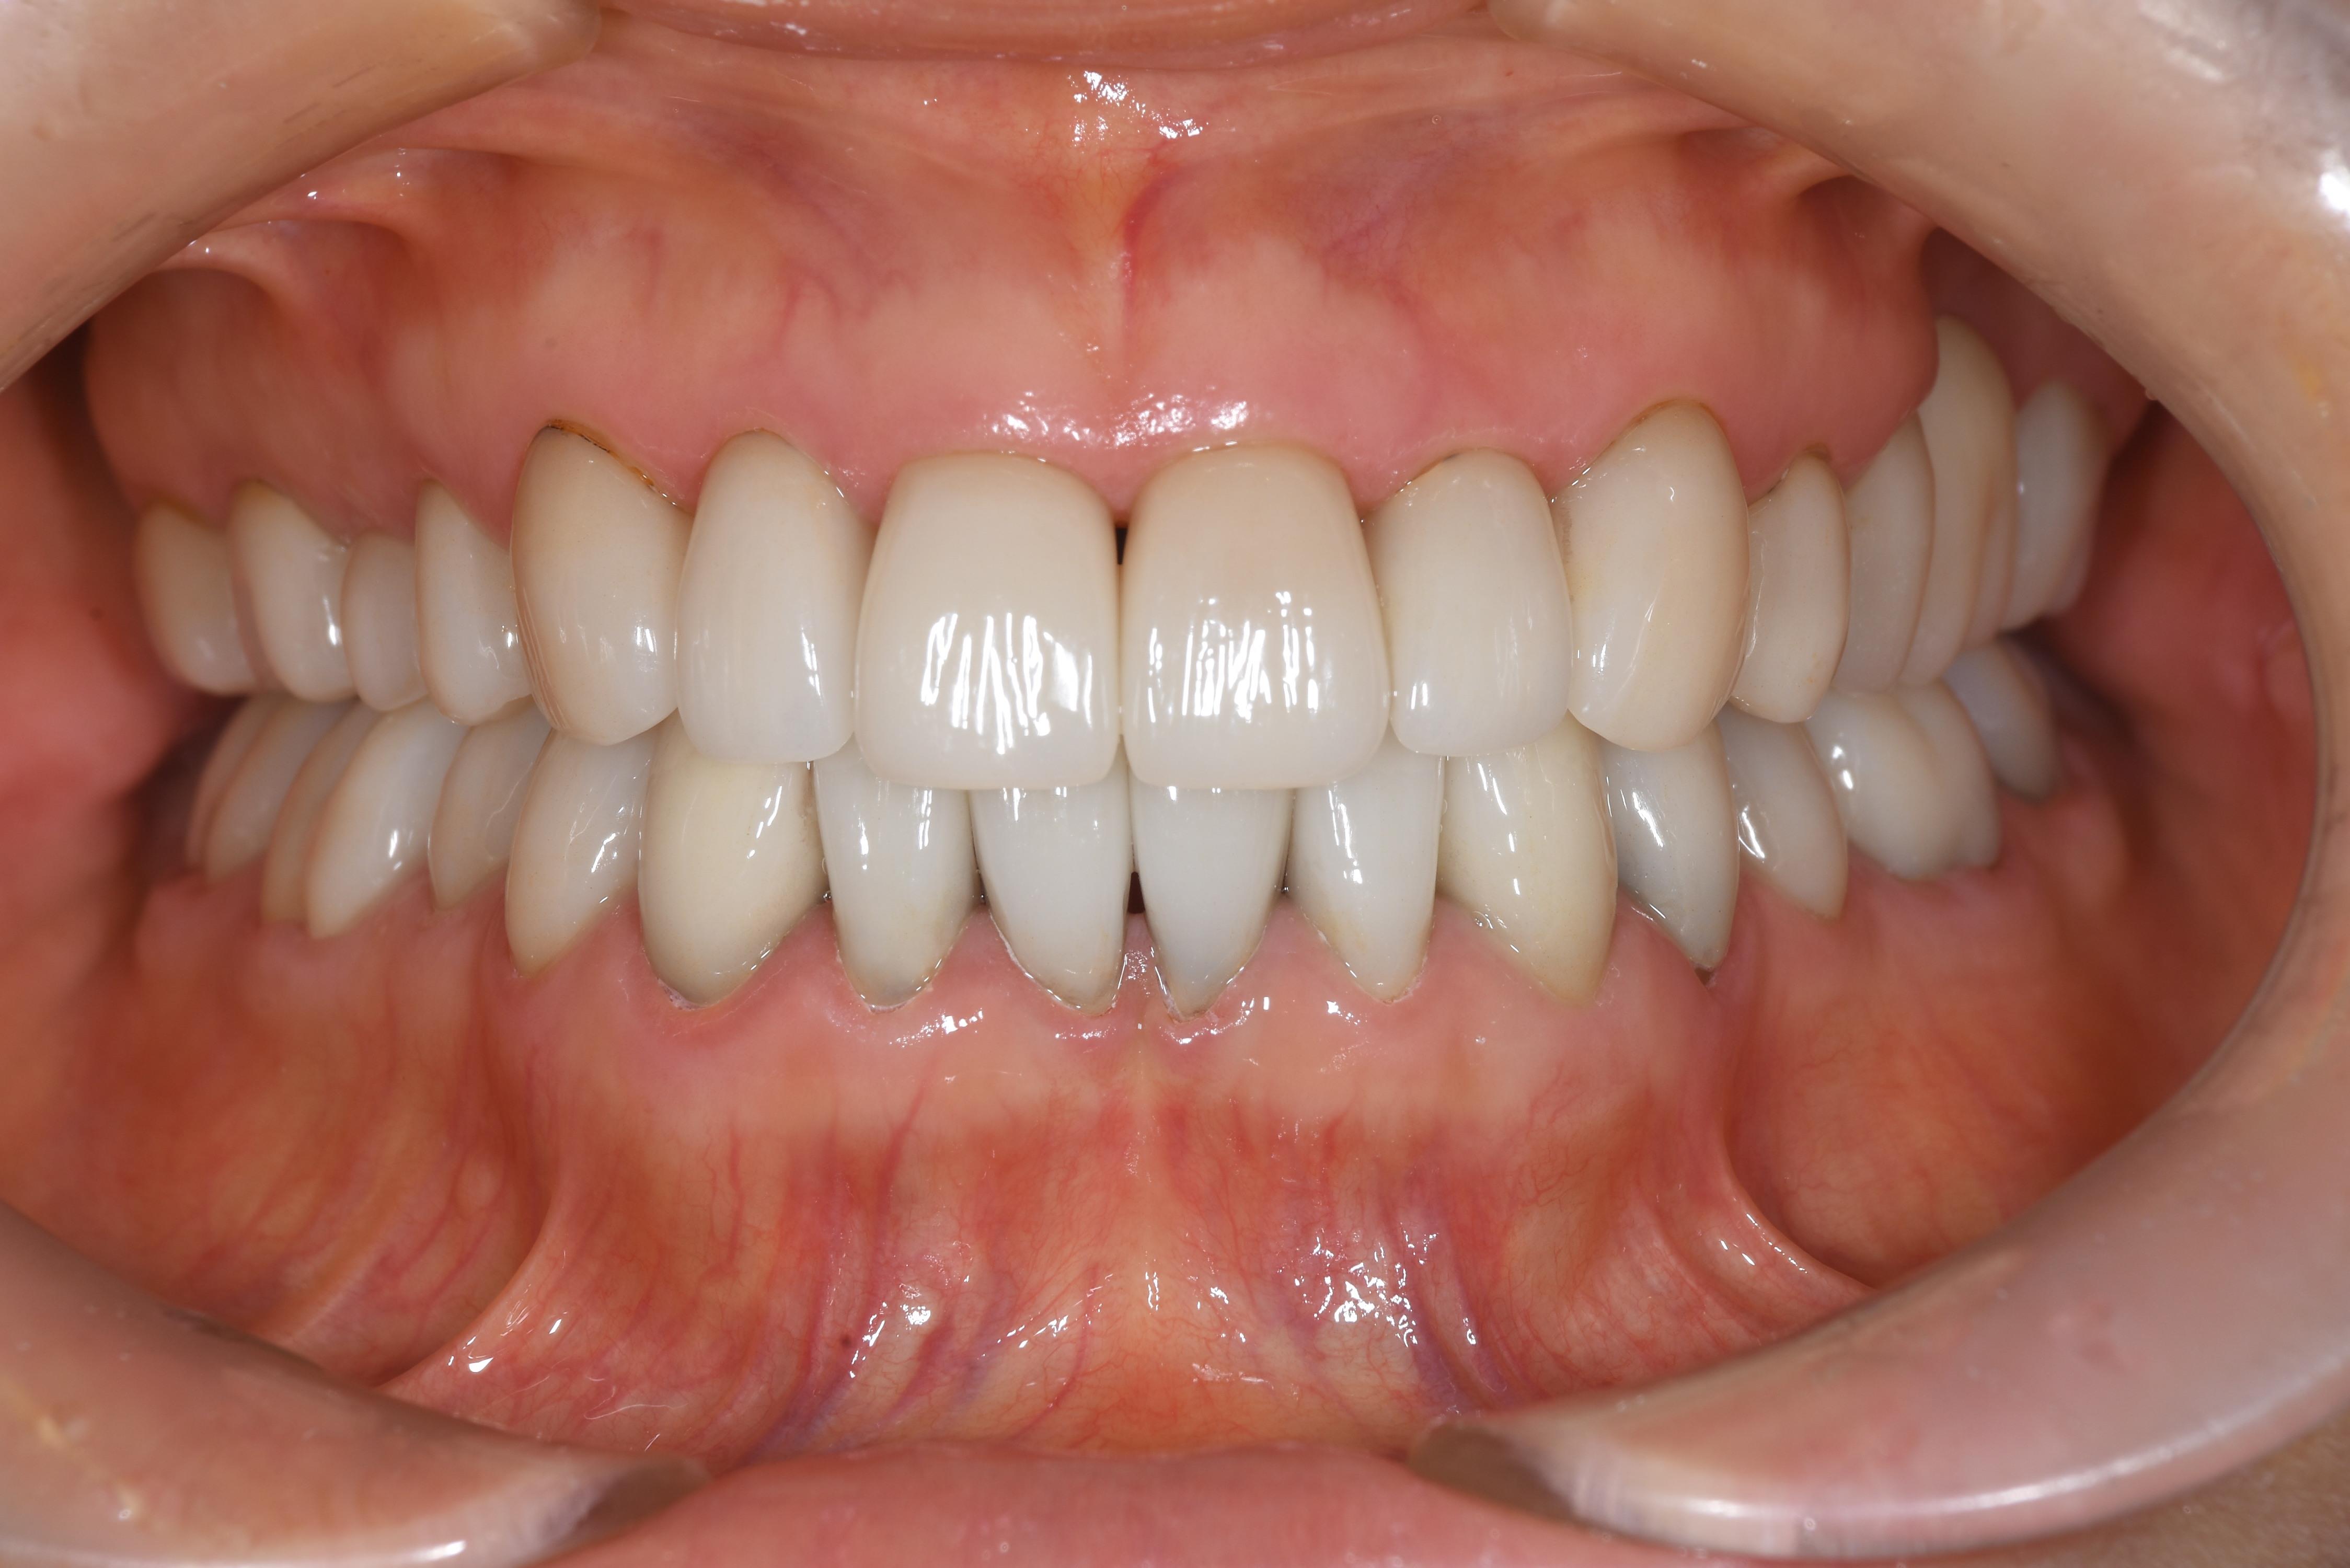

治療後

| 治療内容 | セラミック | 期間 | 約6か月 |

|---|---|---|---|

| 治療回数 | 20回 | 費用 | 約300万(処置費用、仮歯、プロビジョナルを含む) |

| リスク 副作用 |

全て神経を保存して治療しておりますので、セット後に刺激により神経を除去する可能性がリスクとして存在します | ||